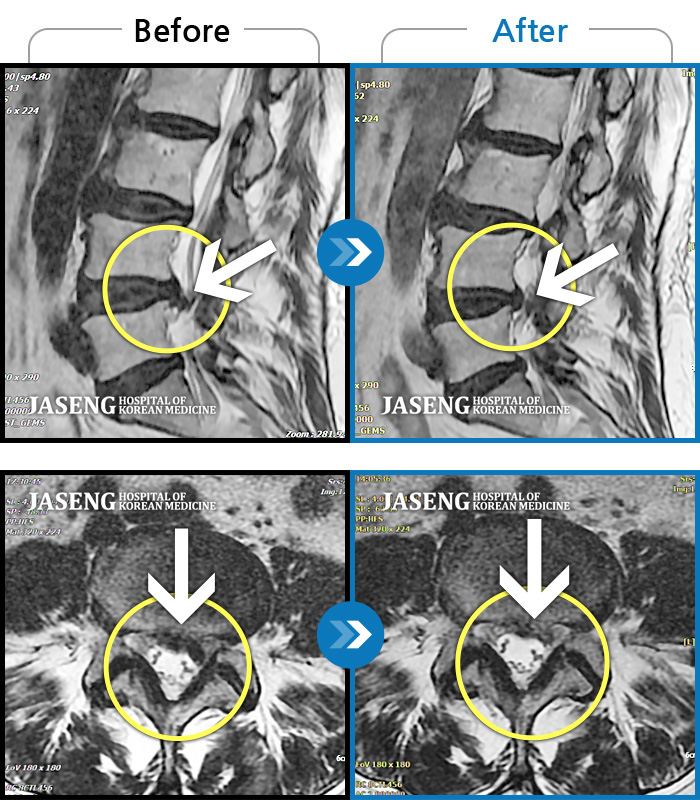

Before

After

환자에게 사전 동의를 받아 동일 조건에서 촬영되었습니다.

개인에 따라 치료 후 부작용이 발생할 수 있으니 의료진과 상담 후 치료를 진행하시기 바랍니다.

우측 허리 및 골반 통증, 우측 다리에 통증과 저림

좌측 다리 측면의 통증으로 입원